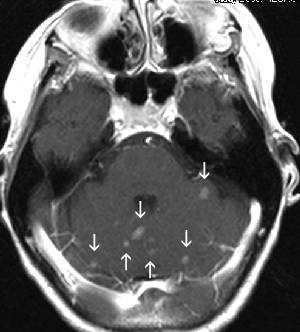

unusual metastases to the midline in the third ventricle, from lung cancer

large cystic brain metastasis from lung cancer

another picture with a small enhancing lesion with

massive edema...was NOT a brain met but

an infection with toxoplasmosis